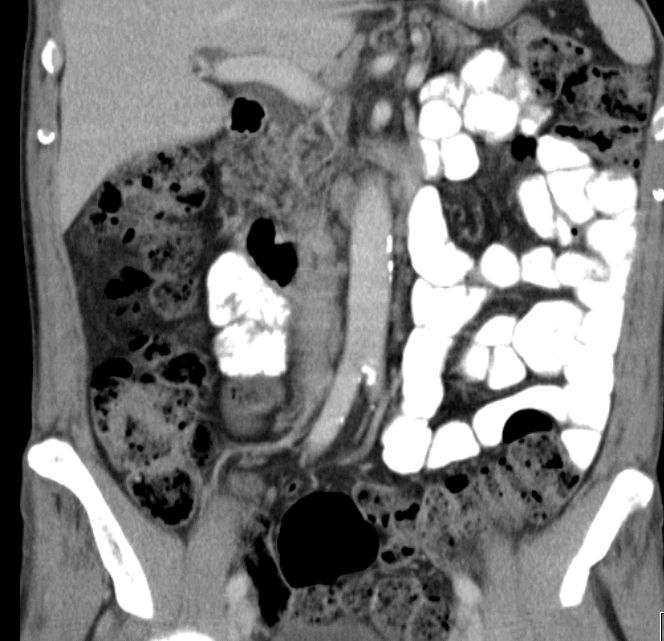

paraaortale Metastasen

Ausgedehnte Lymphnotenmetastasen paraaortal, paracaval und mesenterial